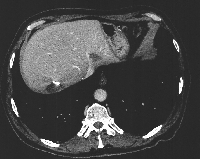

Πρόκειται για ασθενή 75 ετών που διαπιστώθηκε ότι έπασχε από αδενοκαρκίνωμα του σιγμοειδούς με 15 συνολικά ηπατικές μεταστάσεις αμφοτερόπλευρα (εικόνα 1). Η διενέργεια PET-CT δεν ανέδειξε εξωηπατική νόσο. Δεδομένου ότι η πρωτοπαθής εστία τέθηκε υπό προσωρινό έλεγχο με πολυπεκτομή, αποφασίστηκε η αντιμετώπιση πρώτα των μεταστάσεων ("liver first" approach). Με βάση τις εικονικές ηπατεκτομές κατά MEVIS (εικόνα 2) αποφασίστηκε η κάθαρση του ήπατος από το μεταστατικό φορτίο σε δύο στάδια (staged hepatectomy). Ο ασθενής υποβλήθηκε σε 6 κύκλους χημειοθεραπείας (Avastin, FOLFOX). Ακολούθησε δεξιά ηπατεκτομή (εικόνα 3). Κατόπιν υποβλήθηκε σε ακόμα 4 κύκλους χημειοθεραπείας. Η ογκομέτρηση την 4η μετεγχειρητική εβδομάδα ήταν ικανοποιητική (εικόνα 4). Ακολούθησε αριστερή πλάγια ηπατεκτομή (εικόνα 5), η οποία και έφερε την κάθαρση του ηπατικού μεταστατικού φορτίου. Η νέα ογκομέτρηση την 4η μετεγχειρητική εβδομάδα ήταν ξανά ικανοποιητική (εικόνα 6). Συνεχίστηκε η χημειοθεραπεία για ακόμα 4 κύκλους. Ακολούθως, ο ασθενής υποβλήθηκε σε σιγμοειδεκτομή. Τελικά, η χημειοθεραπεία ολοκληρώθηκε με άλλους 6 κύκλους. Ο ασθενής εξακολουθεί να παραμένει ελεύθερος νόσου στους τακτικούς ελέγχους (δις ετησίως) με κολονοσκοπήσεις και CT.